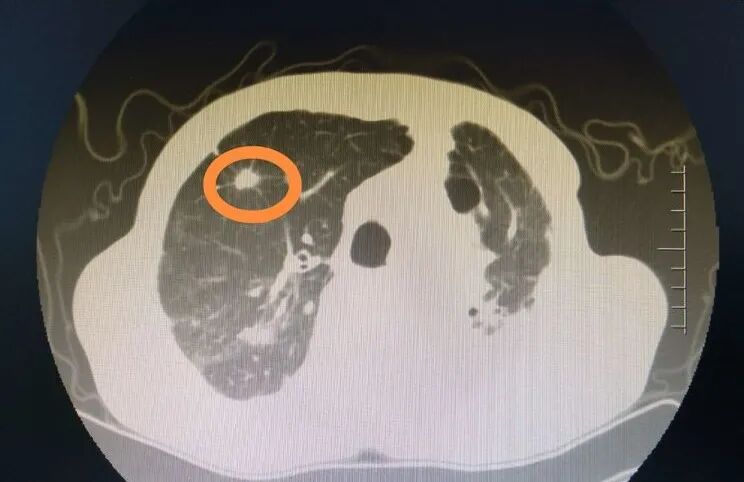

患者男性,65岁,肿瘤早期入院。经过精准化疗后肿瘤未能完全缩小,我科对患者进行全面评估后,决定为患者进行氩氦刀冷冻消融术治疗,于4月10日外请天津医科大学肿瘤医院刘长富教授与我科高栋材医生共同为患者在CT下行氩氦刀冷冻消融术-姑息性局部减瘤治疗。

术前肺癌病灶

刘长富教授与高栋材医生在CT引导下为患者行手术治疗,刘长富教授将直径只有1.7毫米的氩氦刀直击病灶所在“开氩气,降温、降至零下140摄氏度!”氩氦刀的刀头迅速结成冰球,锁定肿瘤细胞,冻结供应营养的血管,摧毁细胞组织,持续几分钟后,氩氦刀迅速又回到常温,经过这样两个循环后,肿瘤经过冰与火的摧残,CT上发现,肿瘤病灶消融区完全被冻结。